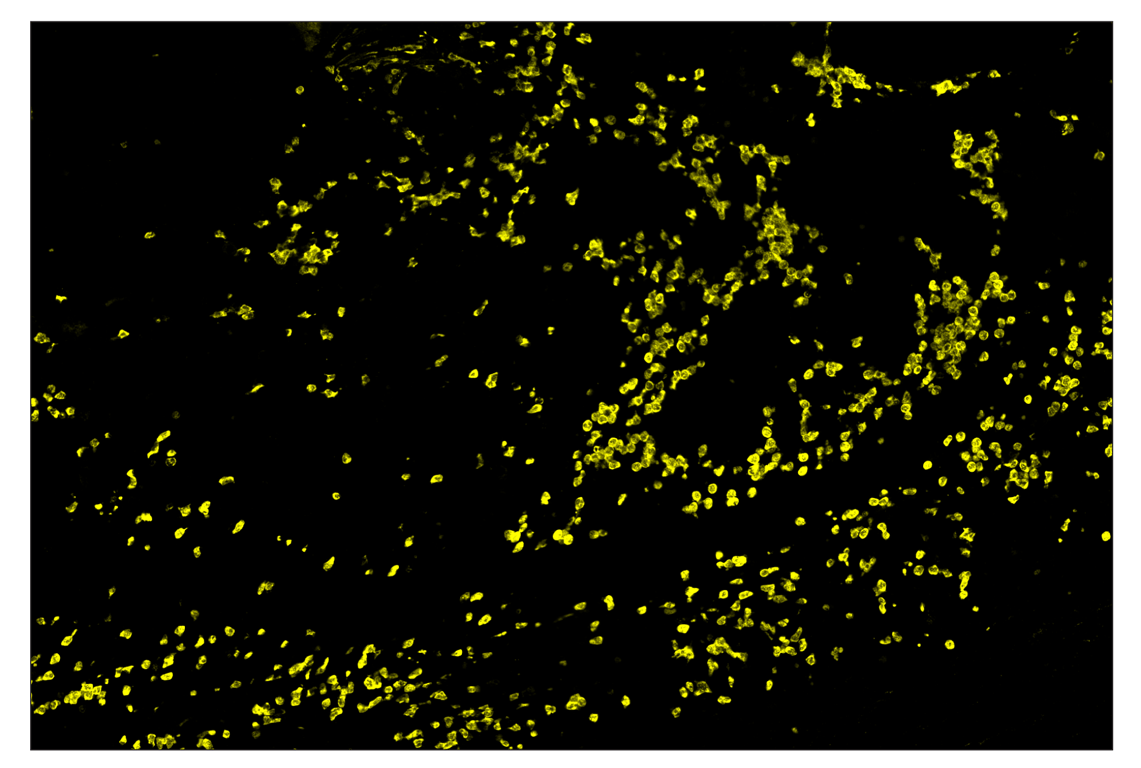

SignalStar™ multiplex immunohistochemical analysis of paraffin-embedded human squamous cell lung adenocarcinoma using CD19 (Intracellular Domain) (D4V4B) & CO-0054-488 SignalStar™ Oligo-Antibody Pair #72855 (green), Arginase-1 (D4E3M) & CO-0075-594 SignalStar™ Oligo-Antibody Pair #66757 (yellow), TCF1/TCF7 (C63D9) & CO-0006-647 SignalStar™ Oligo-Antibody Pair #25502 (red), α-Smooth Muscle Actin (D4K9N) & CO-0024-594 SignalStar™ Oligo-Antibody Pair #25040 (magenta), CD3ε (E4T1B) & CO-0048-647 SignalStar™ Oligo-Antibody Pair #47865 (white), and Ki-67 (D3B5) & CO-0052-750 SignalStar™ Oligo-Antibody Pair #42999 (cyan). All fluorophores have been assigned a pseudocolor, as indicated.

Immunohistochemistry Image 1: Arginase-1 (D4E3M) & CO-0075-750 SignalStar<sup>™</sup> Oligo-Antibody Pair